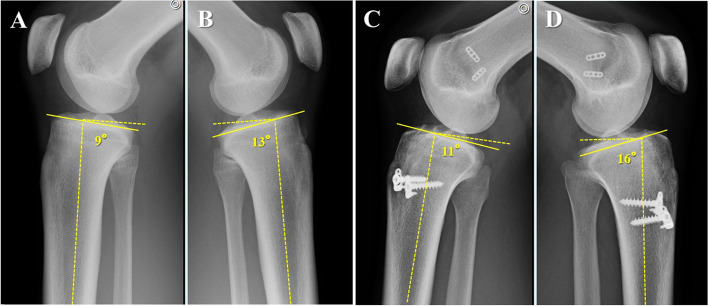

Although PTS has attracted much attention, there are few reports on the laterality of PTS. In our own experience, we have seen several patients with left–right differences in the degree of PTS (Fig. 1), and these patients showed primary ACL injury or re-injury of the graft on the side with a large PTS. This is relevant because if laterality exists in the same patient, it can be used to evaluate the effect of PTS on ACL injury and significantly impact how to prevent postoperative re-injury. The purpose of this study was to examine 1) the degree and frequency of left–right differences in PTS between patients with primary ACL injuries and the control group and 2) the degree and frequency of differences in PTS based on the side of injury and the dominant leg using simple lateral radiographs of both knees in patients with primary ACL injuries. We hypothesized that there exists a left–right difference in PTS, and PTS on the injured side would be greater compared to the un-injured side.

Fig. 1.

A 17-year-old female had an ACL injury in her left knee. A lateral view of the knee shows a PTS of (A) 9° on the right and (B) 13° on the left, with a 4°-difference between the right and left. A 23-year-old woman with bilateral ACL injury after ACL reconstruction. A lateral view of the knee shows a PTS of (C) 11° on the right and (D) 16° on the left with a 5° left–right difference. The right knee joint is clinically stable, whereas the left was re-injured